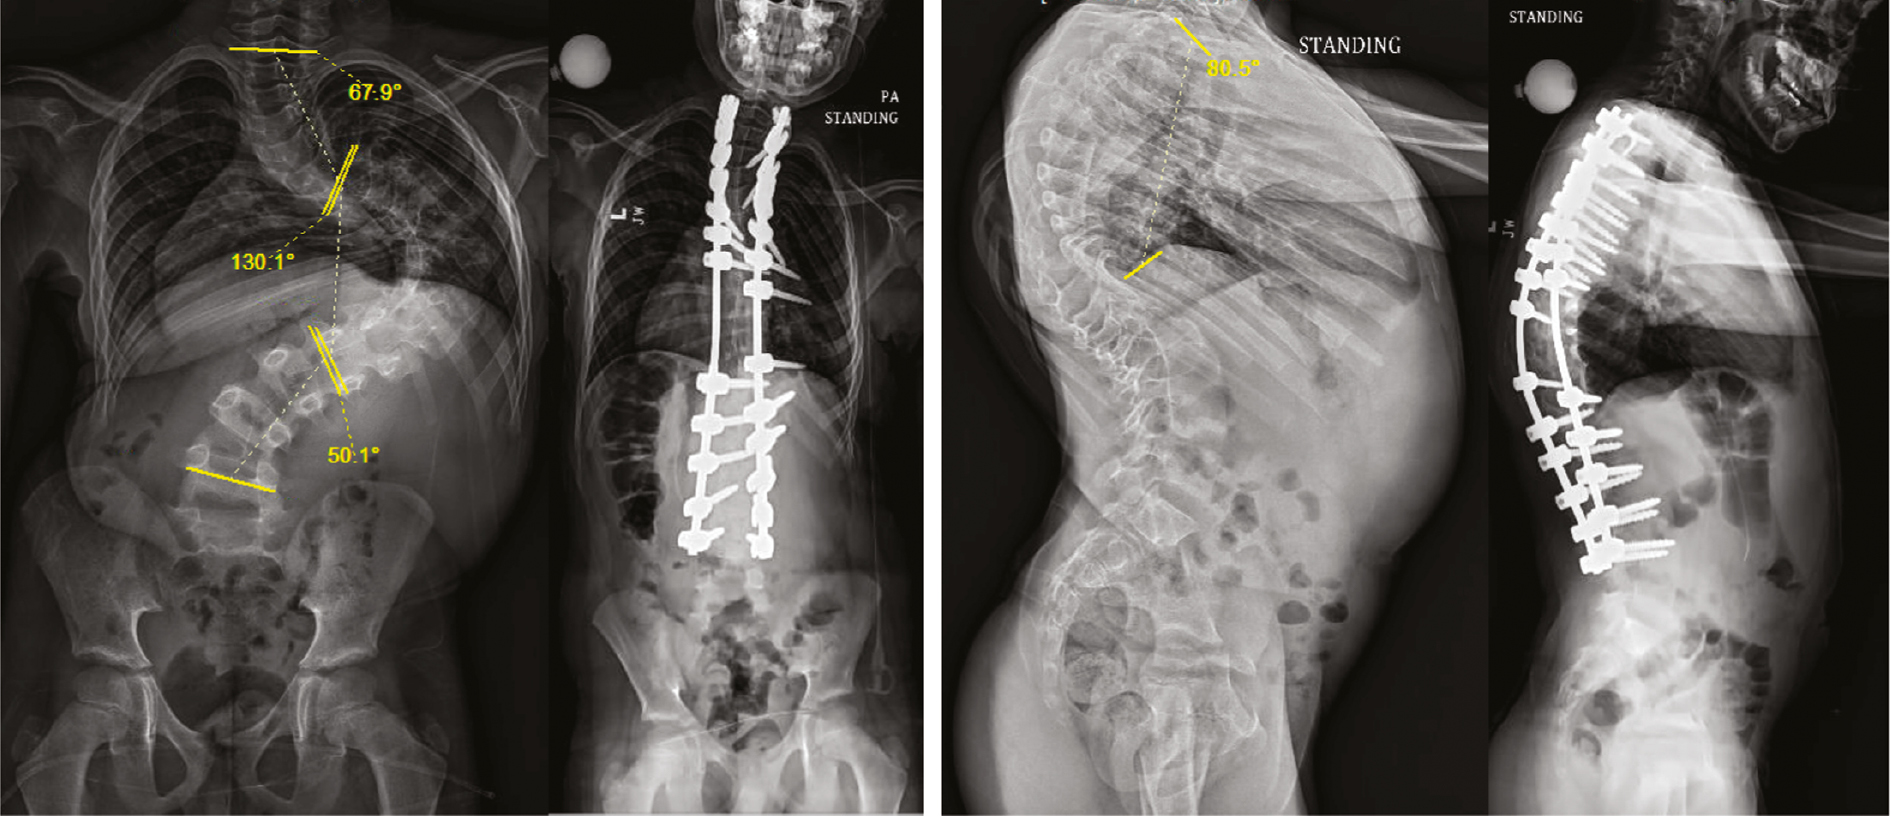

Outside of assessing for preexisting hypotension or anemia which may necessitate pharmacological support or earlier allogenic transfusion, the most important preoperative intervention may be in the planning for deformity correction. Prior planning will always prevent poor performance in the operating room and some forethought about surgical risk factors for spinal cord hypoperfusion can optimize outcomes. We recommend evaluating correction strategies, especially in larger and stiffer curves. Wang et al. have defined the deformity angular ratio (DAR), defined as the curve magnitude divided by the number of levels over which the curve is measured as a risk factor for IONM alerts. Patients with a total DAR (T-DAR), defined as the sagittal (S-DAR) plus the coronal (C-DAR) over 25 or a S-DAR over 15 were more likely to have loss of IONM data intraoperatively (Figure 1).20,21

Figure 1. An 11-year-old boy with severe juvenile idiopathic scoliosis. His Coronal-Deformity Angular Ratio (C-DAR) was 131°/7 levels = 18.7 and his sagittal-DAR (S-DAR) was 80.5°/10 levels = 8.1 giving him a T-DAR of 26.8. He had a temporary decrease in nMEP during correction which responded to removal of apical screws and recontouring the convex rod.